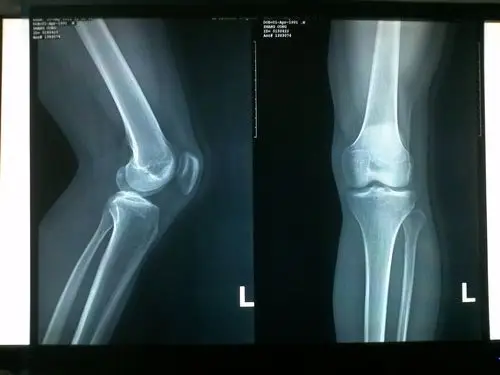

请骨科专家帮我看看这张x关片子骨骺线闭合了没有 谢谢了!

补两张x片